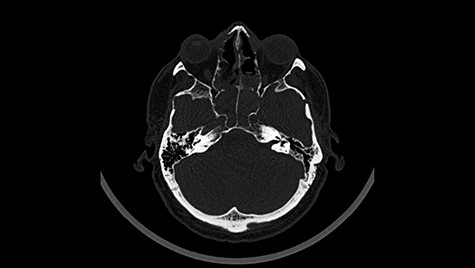

Head CT—state before VP shunt implantation. (Department of Neurosurgery own material).

A 49-year-old patient presented after surgical treatment of nasal polyps, with headache and consciousness disorders (behavioral changes, drowsiness and allophenic orientation disorders). Computed tomography (CT) scan showed (Fig. 1) a presence of blood in fluid spaces, widening of the ventricular system (without active hydrocephalus features) and presence of air in the frontal horns of the lateral ventricles and features of cerebral edema. Due to the subarachnoid hemorrhage, an angio-CT and CT scan was performed, showing no vascular malformation. The patient's condition deteriorated with a drop in Glasgow Coma Scale (GCS) to 9, strongly expressed meningeal syndrome and a fever of > 38°C. In the performed cerebrospinal fluid examination a typical picture for bacterial infection, cultures negative. Treatment was implemented in accordance with the neuro-infections algorithm. Clinical and laboratory features of neuroinfections have withdrawn. The neurological condition of the patient improved to GCS 11. Control head CT (Fig. 2) showed enlargement of the ventricular system with cerebrospinal fluid transudation.

After improvement of patient’s neurological status, a CT scan of the head revealed enlargement of the ventricular system with the features of cerebrospinal fluid transudation (Fig. 2), thus the patient has been qualified for a VP shunt implantation (Fig. 6).